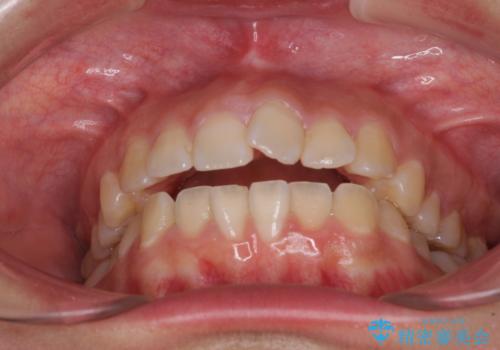

- 上下の前歯が非接触であることと、それに伴う口元の閉じにくさを気にして来院された患者様です。

奥歯の咬み合わせを見ると、上顎が下顎に対して相対的に前方にありました。

口元の閉じにくさを改善するためには、上顎臼歯を後方に移動させた咬み合わせにする必要があります。

インビザライン単体で改善することも可能ですが、達成する可能性が高くないため、カリエールディスタライザーという補助装置を併用して、より確実性を上げることとしました。

奥歯の咬み合わせを改善しながら、並行してインビザラインで歯列を整えることとしました。

カリエールディスタライザーを併用したことで、確実かつ短期間で治療を終えることができました。